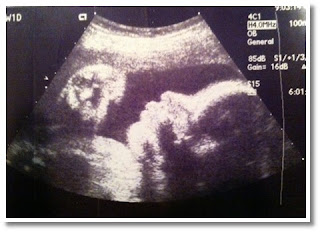

18 weeks after conception (20 weeks LMP), Baby Chris is about the size of a banana at 10 inches long from head to toe and 10 1/2 ounces. Circadian rhythm—the daily cycle of wakefulness and rest—shows up in Baby Chris’s movement and heart rate. You can also spot movement in Baby Chris’s vocal chords as he or she practices the muscle movements that will be necessary to make noise in the outside world.

It’s common for prenatal care providers to offer ultrasounds at this point in pregnancy, so we have an abundance of images this week. Here are just a few. Thank you to everyone who donated!